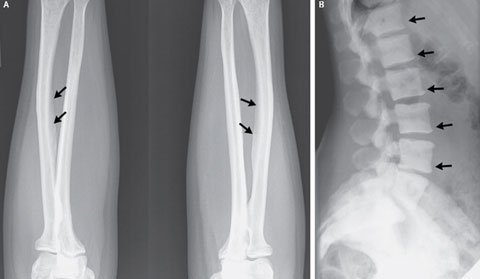

Ảnh chụp X-quang cho thấy người phụ nữ Michigan bị vôi hóa các dây chằng cánh tay và những khu vực xương đậm đặc ở các đốt sống cột sống. Ảnh: Live Science |

Kết quả chụp X-quang hé lộ các khu vực xương đậm đặc ở đốt sống cột sống và sự vôi hóa các dây chằng ở cánh tay của cô, theo tiến sĩ Sudhaker D. Rao, bác sĩ điều trị chuyên về nội tiết, xương và trao đổi chất tại bệnh viện Henry Ford.

Ông Rao và các cộng sự nghi ngờ người phụ nữ đã bị nhiễm độc flour ở xương – một căn bệnh về xương bắt nguồn từ việc hấp thu quá nhiều flour (một khoáng chất có tự nhiên trong trà và nước uống). Hàm lượng flour trong máu của nữ bệnh nhân này cũng cao gấp 4 lần mức bình thường.